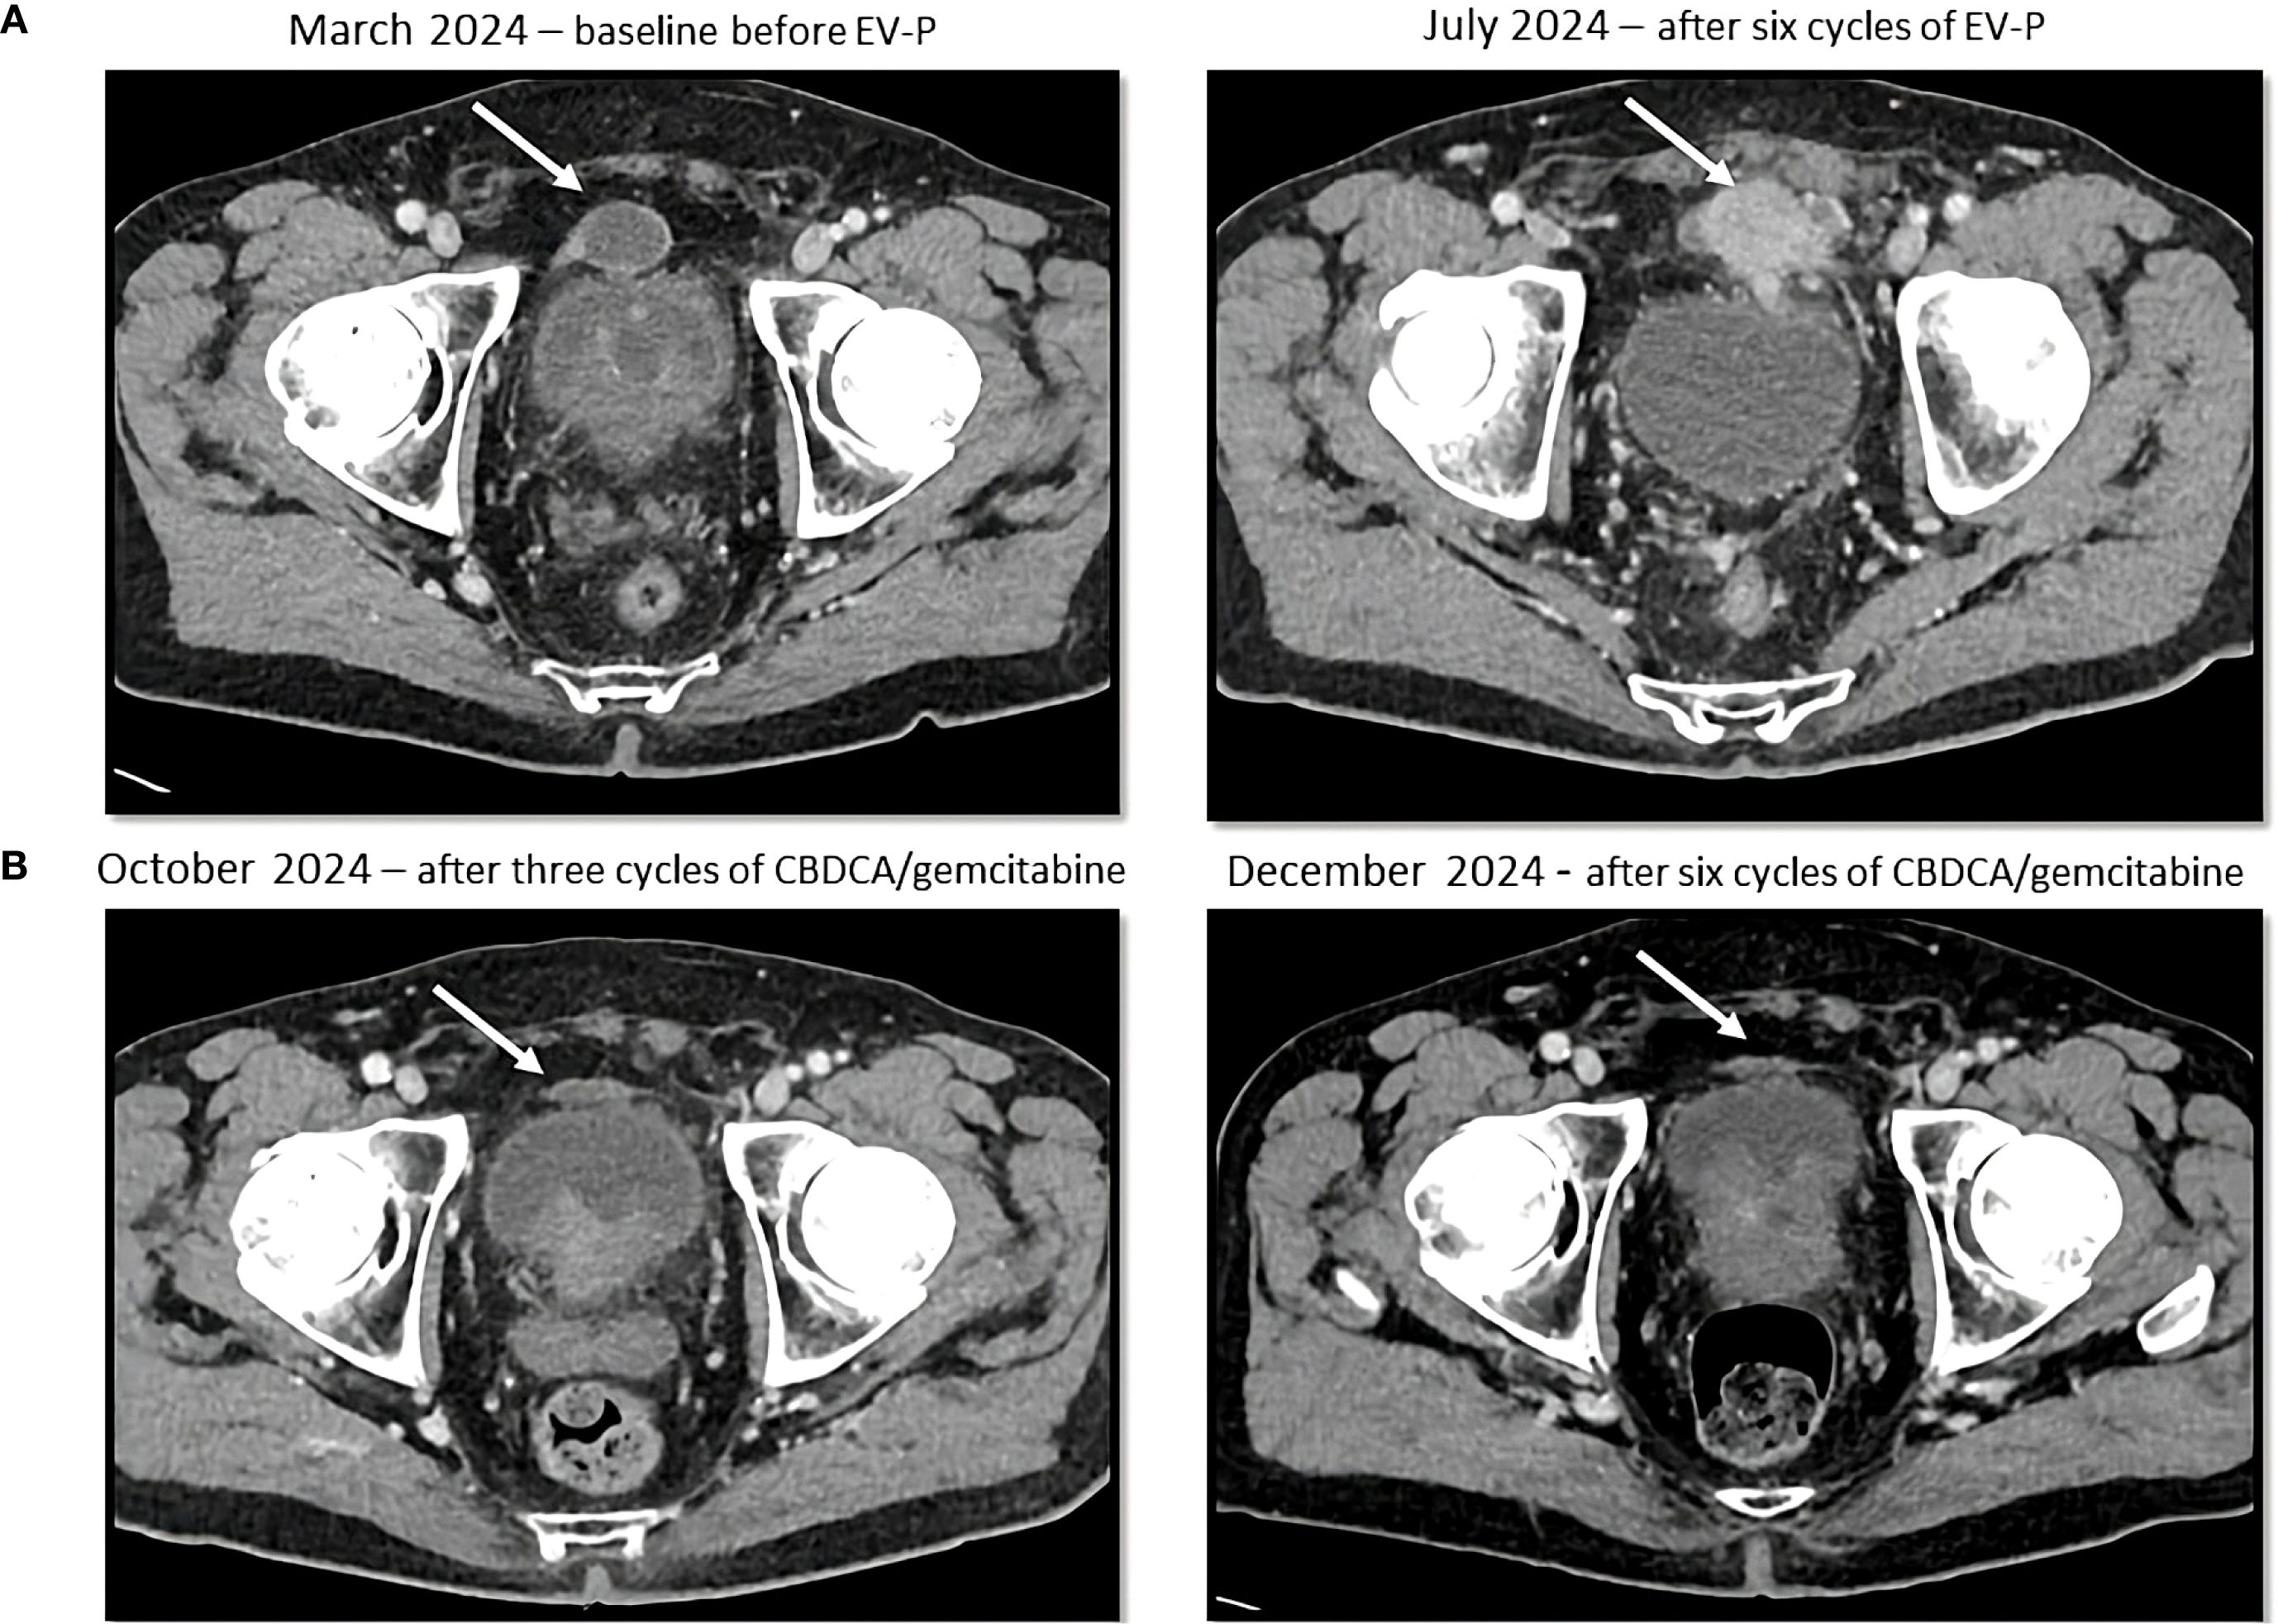

Figure 2

Four-panel medical imaging series of pelvic CT scans. Panel A: March 2024 baseline before EV-P treatment and July 2024 after six cycles of EV-P. Panel B: October 2024 after three cycles of carboplatin/gemcitabine, and December 2024 after six cycles. Each image shows changes in pelvic mass size, indicated by an arrow.

Figure 2. Sequential CT scans showing disease progression during treatment with enfortumab vedotin and pembrolizumab (A) and partial response with platinum-based chemotherapy (B). Cystic lesion (white arrow) above the bladder, that increased in density and size during enfortumab vedotin and pembrolizumab treatment and then decreased in size after platinum-based therapy administration.

The patient was referred to the Oncology Department and in March 2024 started first line EV-P treatment. A CT scan was performed after the administration of the third cycle of the treatment and showed a RECIST 1.1 partial response (PR), with reduction in pyelo-ureteral lesions and peritoneal nodules, as well as a complete resolution of the ascites. However, a single pre-vesical peritoneal lesion had increased in size (8mm diameter increase, from 13 to 21 mm). A follow-up CT after three additional cycles (July 2024) demonstrated progressive disease, with new peritoneal lesions, suspected left pyeloureteral junction disease relapse, and an enlarged right obturator lymph node (Figure 2A). EV-P treatment was therefore discontinued after six cycles. All treatment cycles were administered without dose reduction or delay. During the treatment, the patient developed grade 1 oral mucositis and peripheral neuropathy.

A CT scan after three cycles (October 8, 2024) showed a PR by RECIST 1.1 with a significant reduction in tumor burden with a reduction in size of numerous peritoneal lesions (the biggest being the aforementioned prevescical lesion that decreased from 46 mm to 31 mm) and of the right obturator lymphadenopathy (with a short axis from 10 mm to 6 mm). The case was subsequently discussed at our multidisciplinary board which, due to the good treatment response, suggested continuing treatment with carboplatin and gemcitabine for up to six total cycles. Subsequent cycles were administered at a reduced dose (25% dose reduction for both drugs), due to grade 2 anemia and grade 1 peripheral neuropathy. The CT scan performed after six cycles (December 18, 2024) confirmed an even deeper response, with complete response of some peritoneal nodules (Figure 2B). A follow-up CT scan in March 2025 further demonstrated the stability of the achieved response.